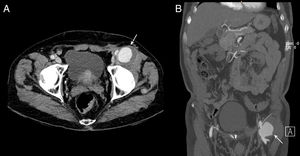

Presentamos un paciente que desarrolló un pseudoaneurisma de la arteria femoral común (AFC) tras hernioplastia inguinal mediante técnica de Lichtenstein, probablemente con relación a la fijación de la malla en la cirugía (fig. 1).

El paciente fue intervenido por Cirugía Vascular objetivando ruptura de la pared posterior de la AFC y colocándose un injerto con anastomosis término-terminal.